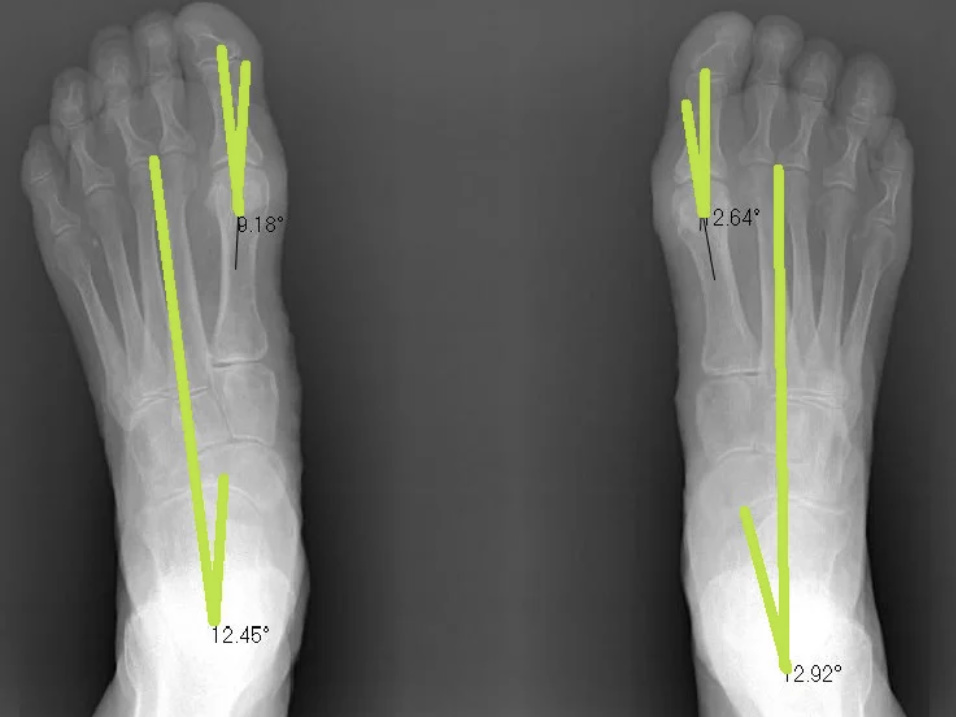

Below is Margaret Perry's before and after x-rays. Margaret had tried orthotics but found they were extremely limiting as they didn't fit in her shoes and didn't improve her foot pains.

We completed a course of Foot Mobilisation Therapy, which is a hands on technique that gently corrects the alignment of the foot and lower leg.

You can clearly see the joint misalignment has improved and she is standing straighter . Her bunion angles have reduced and the bone (talus) in her ankle has repositioned into a normal position which is between 12-18 degrees!